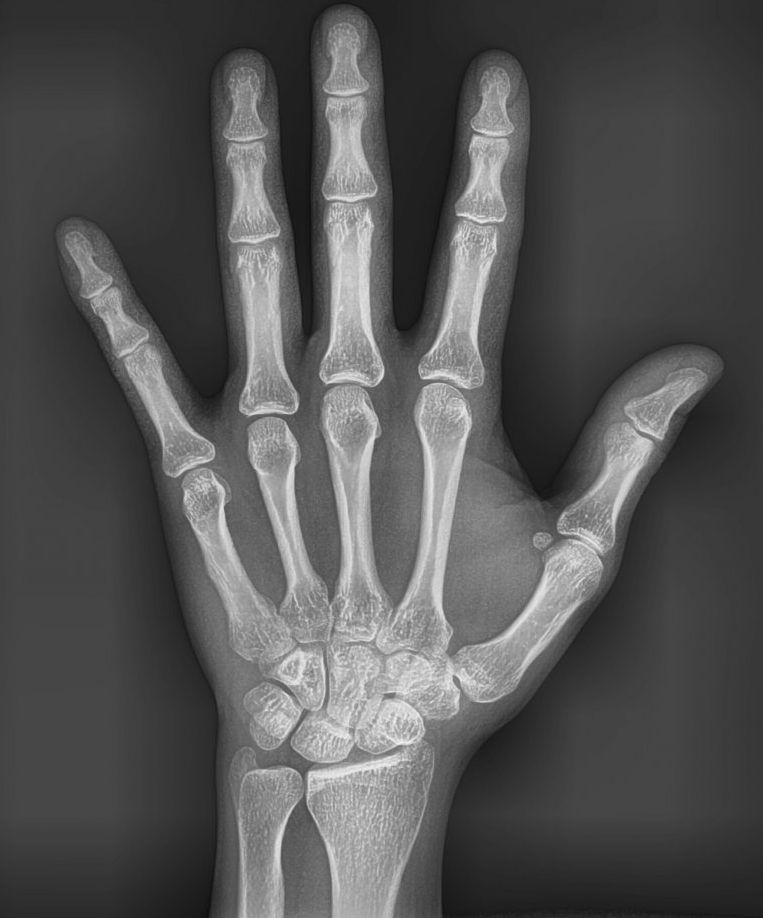

Radiografía carpal digital

Estudio de rayos X de la mano y muñeca utilizado principalmente para evaluar la edad ósea y el desarrollo esquelético de un individuo.